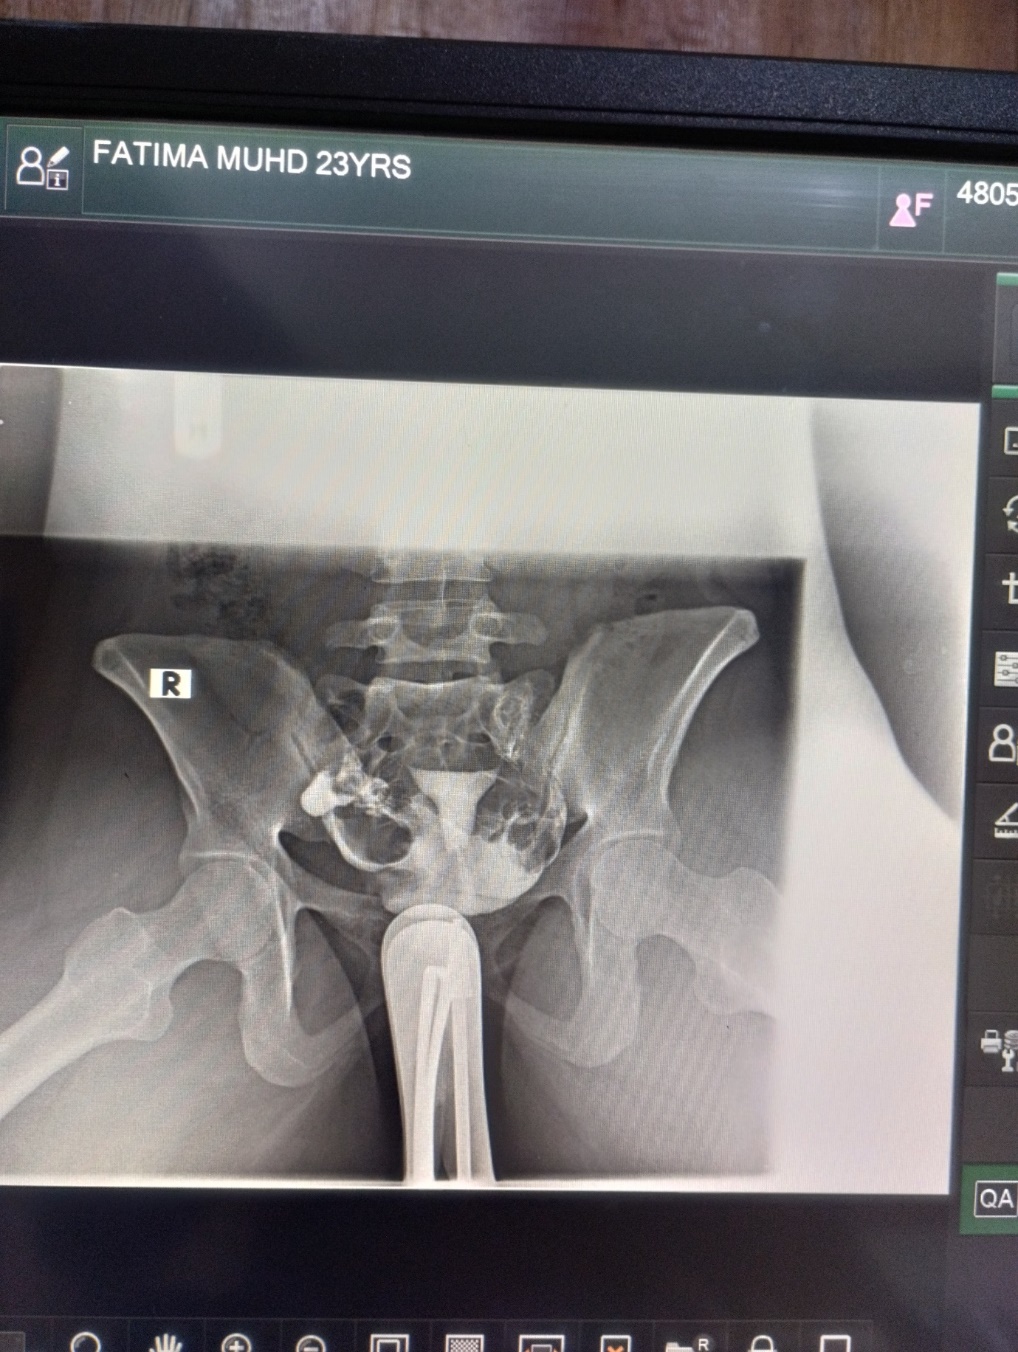

Figure 1: shows normal HSG with bilateral patent fallopian tubes

One hundred and twenty-five (41.7%) patients had normal HSG findings; this indicates that there was no structural abnormality detected in the cervical canal, uterine cavity and both fallopian tubes. This finding is consistent with a study in Sokoto, North-West Nigeria, which reported a comparable prevalence of normal findings15. However, it is higher than the findings recorded in Maiduguri, North-Eastern Nigeria16 and Korle-Bu, Ghana14. The relatively higher prevalence of normal findings in this study might be attributed to the therapeutic effects of the HSG procedure, which is known to resolve certain mild tubal blockages, resulting in normal imaging appearances14.